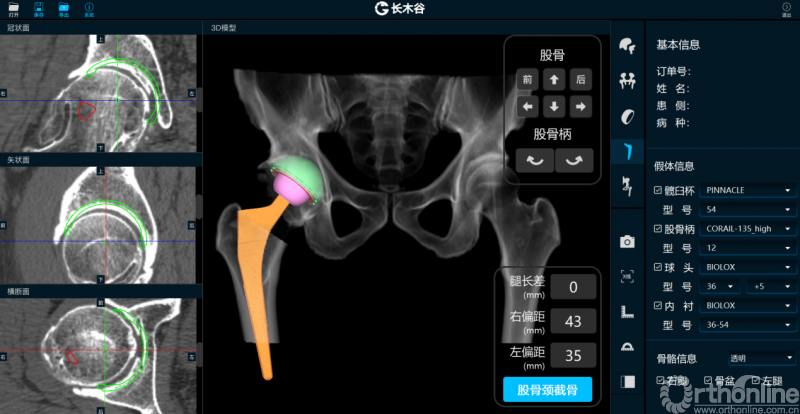

AI HIP系统对患者术前偏距与腿长差进行智能测量与评估

而后,由人工智能判断患者双侧腿长差及股骨偏心距大小,如图可见,由于长期受到的髋关节撞击征影响,该患者术前腿长差为2mm,右侧股骨偏心距为43mm,明显大于左侧股骨偏心距35mm。

AI HIP系统智能安放54mm直径的强生Pinnalce髋臼杯

最后,AI HIP系统根据患侧股骨颈干角、偏心距偏大的特殊情况,智能选择使用高偏高颈干角假体,对下肢等长和等偏心距重建做出了精准设计。根据系统预测结果,术中使用54mm Pinnalce髋臼杯、12号CORAIL高偏股骨柄、36mm 陶瓷股骨头、小转子上23mm截骨,实现髋关节的个体化、精准化重建。